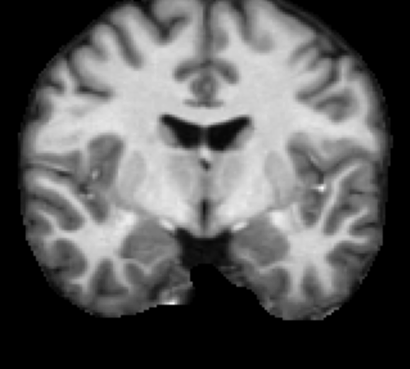

Inverse consistent rigid, affine, nonparametric, and MLP registration. We train networks on MNIST 5s using the methods in Secs. 3 and 4, demonstrating that the resulting networks are inverse-consistent. Our TwoStepConsistent (TSC) operator can be used on any combination of the networks defined in Sec. 3. For demonstrations, we join an MLP registration network to a vector field registration network, and join two affine networks to two vector field networks. Fig. 2 shows successful inverse-consistent sample registrations.

| Moving Image | Warped Image | Fixed Image | Moving Image | Warped Image | Fixed Image |